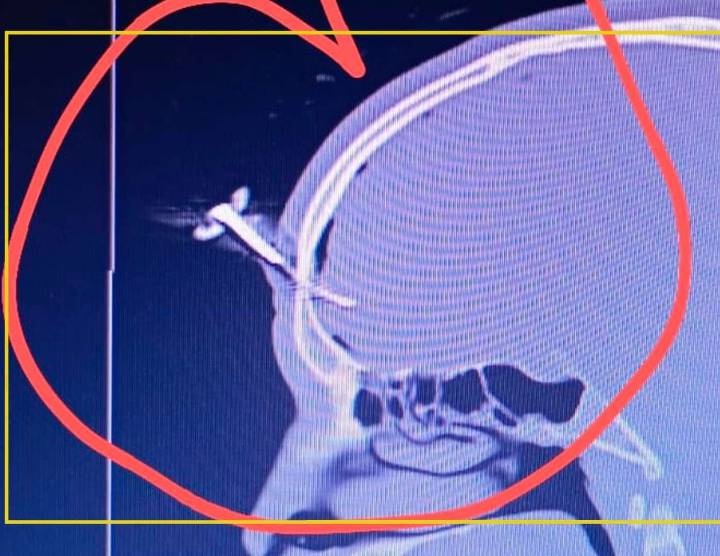

Un partido de fútbol femenino juvenil en Gimnasia y Esgrima de Villa España terminó con una batalla campal y un hombre fue apuñalado con una llave de auto en el cráneo.

Se trata de Jonathan Smith , un exfutbolista de la Asociación Deportiva Berazategui que ya fue operado y se encuentra internado en el Hospital Evita Pueblo de Berazategui.

Hubo discusiones entre padres y allegados y cuando Smith intentaba defender a un amigo apareció en escena el agresor y el Corto fue apuñalado con una llave de auto en el crán